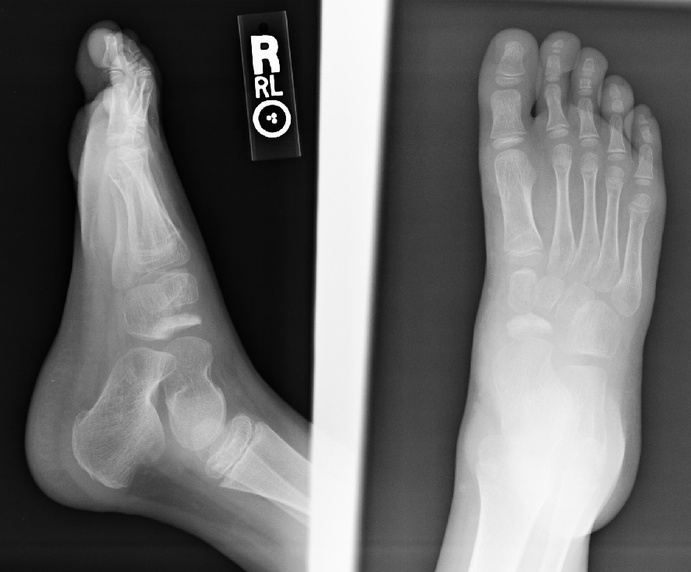

1. Describe the main finding.

2. Do you have a diagnosis? a differential diagnosis?

3. What is the etiology of the pertinent finding?